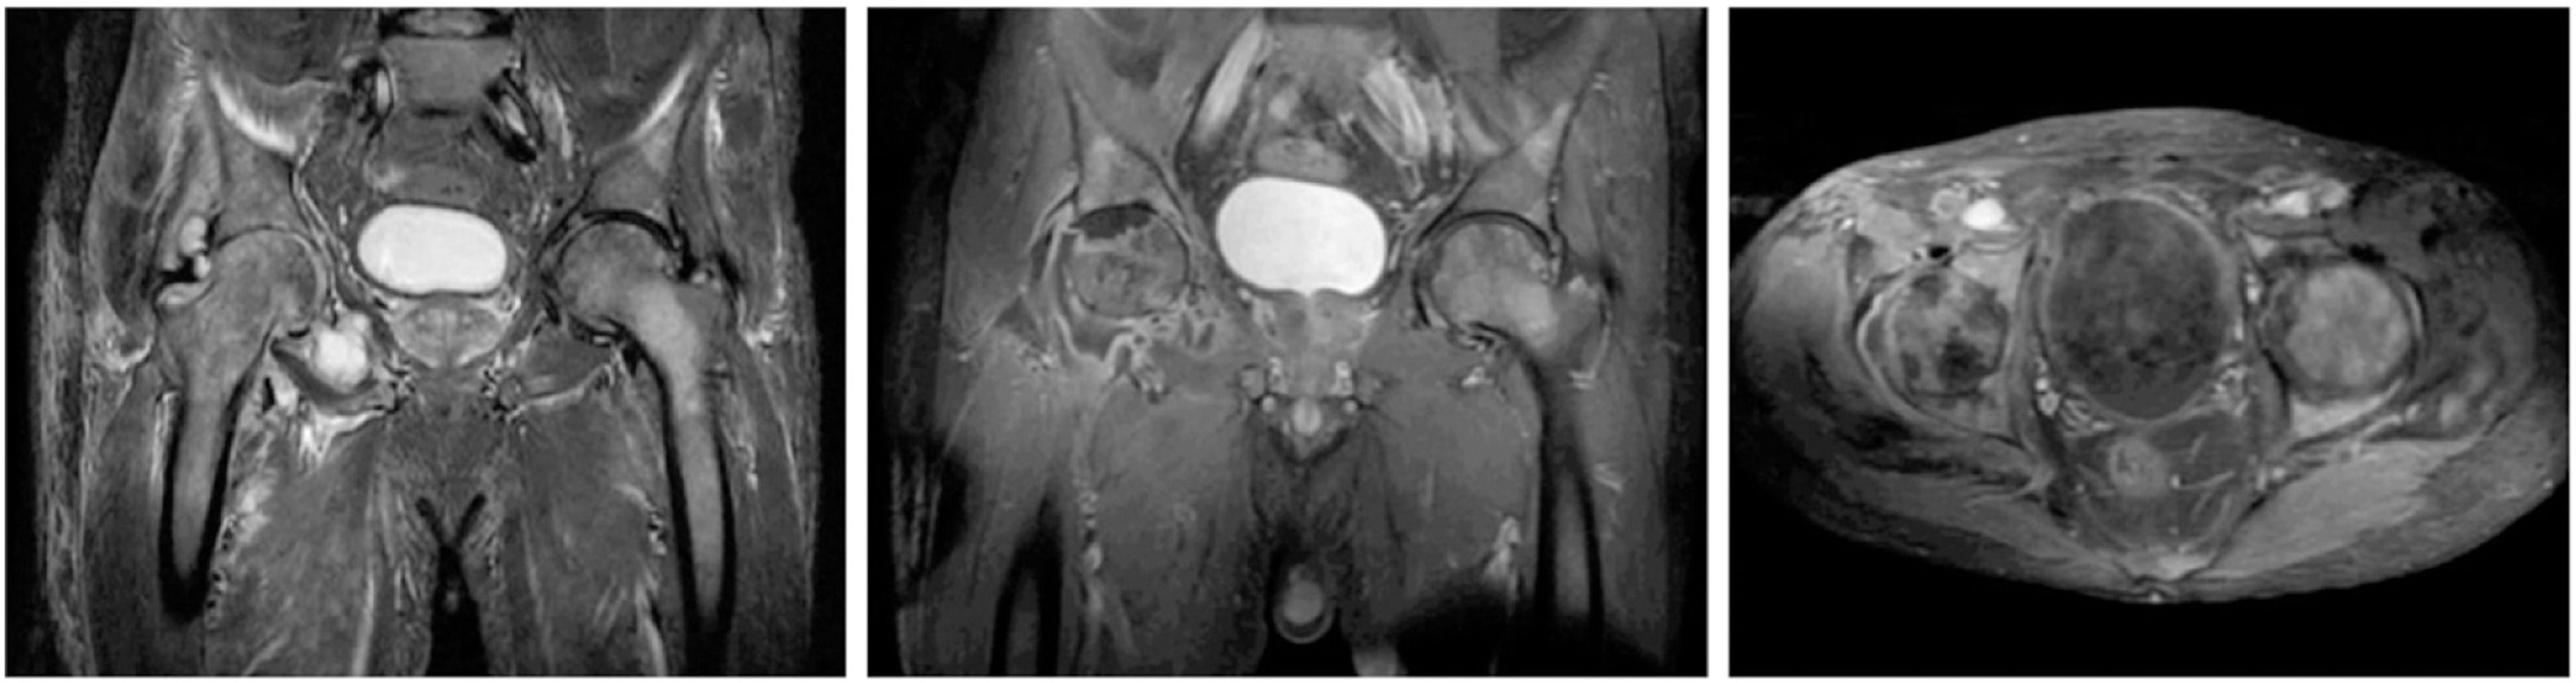

Abdominal computed tomography demonstrated splenomegaly (16 cm longitudinal axis). Magnetic resonance imaging of the pelvis and right knee revealed avascular necrosis of the right femoral head without loss of sphericity, associated with chondral thinning and joint space narrowing. A large right hip joint effusion was present, with distension of the articular recesses and capsular enhancement after contrast. Edema of the gluteal muscles and proximal thigh was noted, along with diffuse bone marrow infiltration of the pelvis, sacrum, evaluated vertebral bodies, and both femurs (Figure 1).

Magnetic resonance imaging of the pelvis showing avascular necrosis of the right femoral head, chondral thinning and narrowing of the right hip joint space, large right hip joint effusion with distension of the articular recesses and capsular enhancement after contrast administration; in addition to edema in the gluteal muscles and the proximal right thigh, along with signs of bone marrow infiltration of the pelvis, sacrum, studied vertebral bodies, and bilaterally of the femurs.